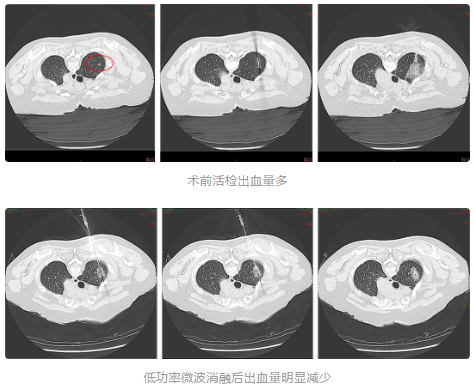

GGO消融后活检病例展示

病例展示

女性患者,56岁,肺部原位腺癌切除史,随访过程中发现GGO在增大。

术前活检取出的组织量少。

低功率微波消融后活检取出的组织量明显增多,紧密。

术前活检病理结果为阴性,低功率微波消融后病理结果为阳性。